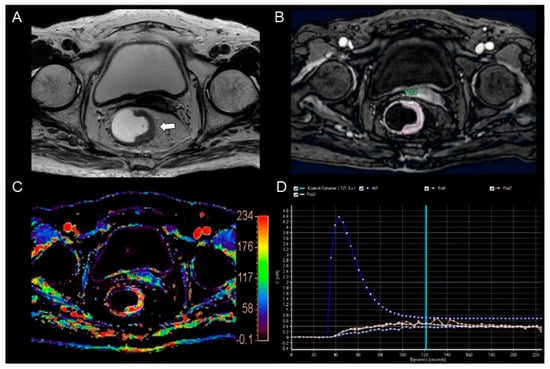

Figure 2.

MR images from an 86−year−old woman with pathologically proven well−differentiated rectal adenocarcinoma. (A) The T2−weighted axial image shows an ulcero-infiltrative mass (arrow) in the left wall of the mid rectum. (B) The post−contrast axial 3−dimensional spoiled gradient echo image shows a relatively hyper−enhancement in the corresponding tumor. (C) The color−coded Ktrans map shows a predominantly red color in the corresponding tumor. The calculated mean Ktrans was 0.137 min−1. (D) The concentration time curve shows a plot of arterial input function (AIF, blue line), which was incorporated automatically with the population−based data and three plots from the consecutive three regions of interest (ROIs−1, 2, and 3) in the whole tumor (pale blue and orange lines).